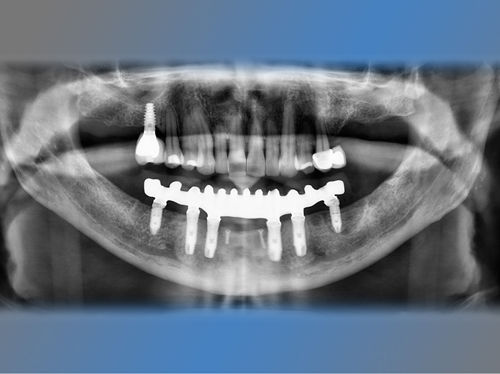

Se optó por colocar 5 nuevos implantes al mismo tiempo que se regeneraba su mandíbula con un injerto óseo. Se utilizaron 4 de estos implantes para ponerle una prótesis fija provisional al cabo de 24 horas (carga inmediata).

La cirugía se realizó bajo sedación consciente intravenosa por un médico anestesista, y fue muy cómoda para Joaquín, tal y como él nos cuenta. Tres meses después la prótesis provisional se cambió por una prótesis definitiva reforzada y más extensa al estar soportada esta por 6 implantes dentales.